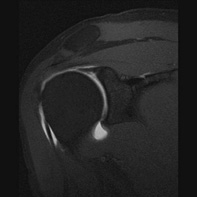

MRI: Not recommended in older patients solely for identifying SLAP lesions. SLAP lesions in older patients are largely asymptomatic and MRI can lead to overdiagnosis. MRI is useful in younger patients (<35 years old) and can be made even more sensitive with the use of contrast (MR arthrogram).

Image 9 [12]. The labrum is seen as a dark triangle in a normal shoulder. SLAP tears are evidenced by bright signaling where there would otherwise be a lack of signal.

Image 10 [12]. SLAP tear indicated by white signal in what would normally be a pure black triangle of the labrum.